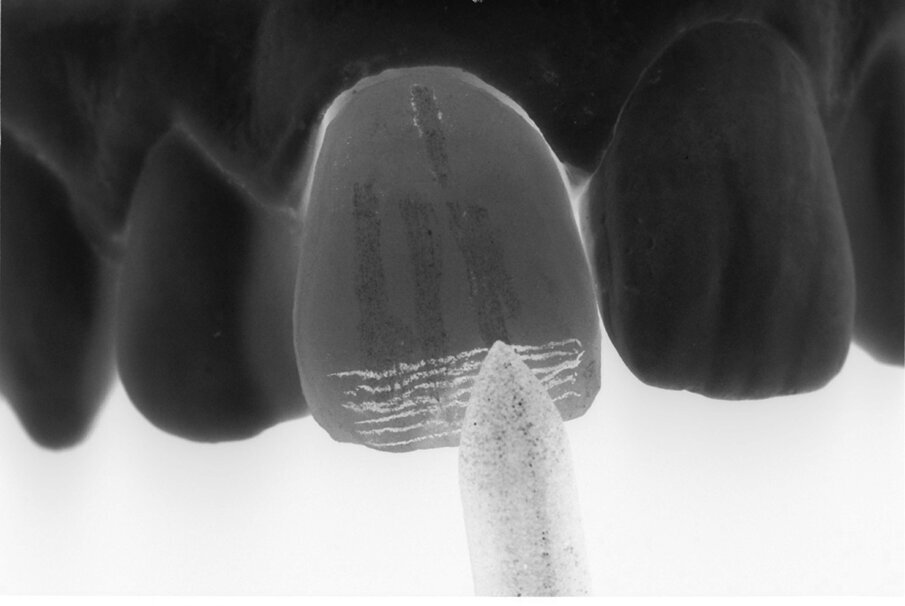

La texture della superficie è una proprietà ottica del materiale ceramico e ha un valore fondamentale per esaltare l’aspetto estetico dei restauri protesici realizzati con questo materiale. La forma contiene quindi la funzione, il colore e la superficie del materiale ceramico. La luminosità, la rugosità e la qualità dei segni applicati sulla superficie di un dente influiscono sulla rifrazione della luce, che può variare a seconda della disposizione di queste caratteristiche. Le linee di tessitura che attraversano la superficie di un dente non hanno tutte la stessa direzione (Fig. 1). Sono orizzontali, verticali e oblique; a volte si può avere una combinazione di queste caratteristiche che esaltano l’aspetto vestibolare. Un dente con la stessa configurazione vestibolare ma con linee di tessitura diverse sulla superficie cambia continuamente aspetto estetico (Fig. 2).

Fig. 1 - Direzione del fascio luminoso dei fenomeni di rifrazione e riflessione.

Fig. 2 - Denti della stessa forma e della stessa consistenza hanno molteplici aspetti. Le superfici concave e convesse del dente accoppiate a linee di diversa direzione consentono diverse combinazioni della texture desiderata.

Questo dimostra l’importanza del modo in cui viene eseguita la texture, caratteristica che viene levigata manualmente dopo la smaltatura della ceramica al fine di ottenere una tessitura superficiale adatta al restauro estetico da effettuare. La texture può essere creata con segni più spessi e sottili: la combinazione di questi spessori permette di ottenere un risultato di texture variabile su tutta la superficie del dente (Figg. 3-5).

Figg. 3-5 - Stessa tecnica di tessitura eseguita su materiali diversi: denti in ceramica e in resina.